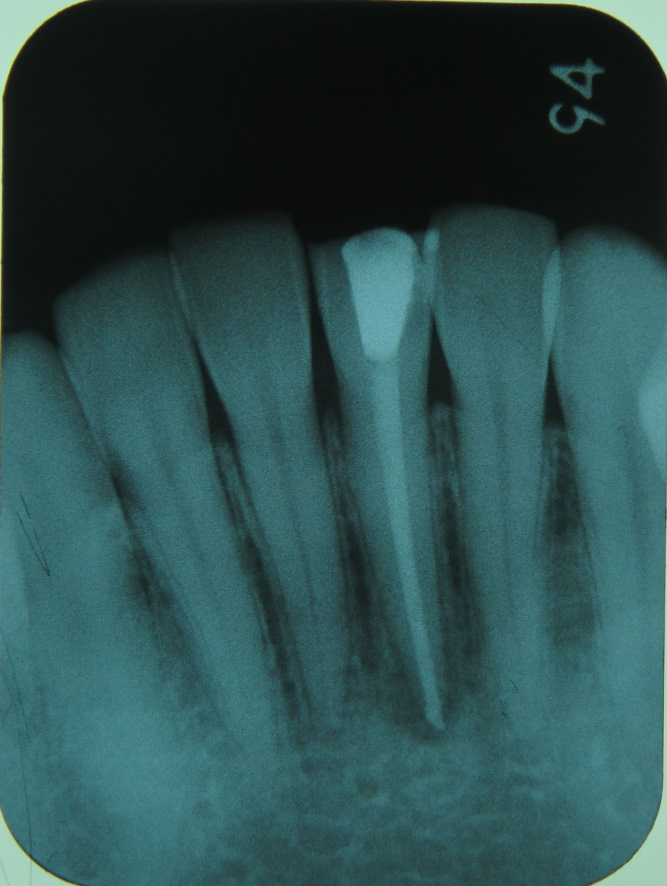

①レントゲンで確認し、被せ物が入っていたら除去する。このレントゲンでは、前回治療された根管充填が

不十分だということがわかります- ②前回、根管治療で詰めたゴム状の充填材や感染の原因となるものを除去する。当院では、超音波洗浄やco2レーザー・薬剤などを用いて根管内が無菌状態になるまできれいに処置します